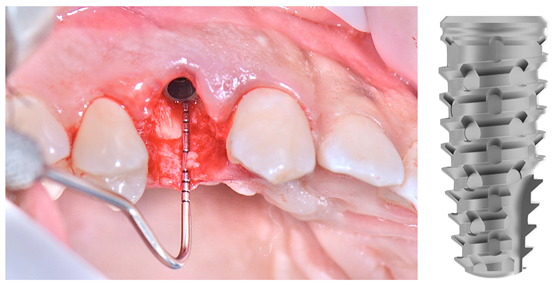

Após o diagnóstico e planejamento, baseados em exames radiográficos e clínicos (Figuras 1 e 2), a primeira etapa foi realizar uma extração dentária atraumática (secção dentária e utilização de periótomo fino e flexível), visando a preservação completa do periodonto de sustentação. Após a curetagem para remoção total da lesão periapical, fez-se a instalação do implante alcançando-se um ótimo travamento inicial e um correto posicionamento ápico/coronal e tridimensional (Figura 3). O Túnel Check, da Implacil De Bortoli (Figura 4), foi utilizado para avaliar o posicionamento tridimensional do implante e selecionar a altura correta do cicatrizador – optou-se por um cicatrizador ao invés do parafuso de cobertura do implante para que não houvesse formação óssea sobre o parafuso, o que tornaria a reabertura muito mais traumática. Após, a membrana Cytoplast TXT 200 Singles (Implacil De Bortoli) foi personalizada e instalada inicialmente na face palatina (Figura 5 – ela não deve ficar tocando nas faces proximais dos dentes vizinhos), seguido do preenchimento alveolar (Figura 6) com substituto ósseo natural contendo 25% de colágeno, o Extra Graft XG-13 (Implacil De Bortoli). Por conter colágeno na sua composição, o Extra Graft XG-13 não fica liberando as partículas ósseas ao longo do processo de osteointegração.